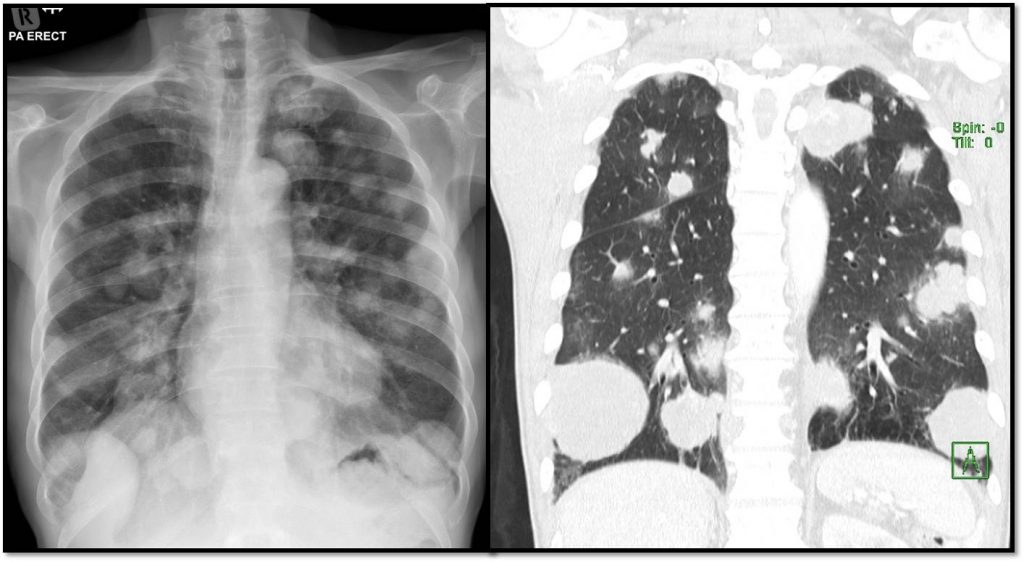

Healthcare Free FullText Pneumocystis Pneumonia in a Lung Cancer Golf Ball Size Tumor In Lung however, any rapidly growing mass should be suspected of being cancer until proven otherwise. a lung mass is defined as an abnormal spot or area in the lungs larger than 3 centimeters (cm), about 1.5 inches, in size. Spots smaller than 3 cm. researchers have found that your primary (main) tumor size may affect your survival with. Golf Ball Size Tumor In Lung.